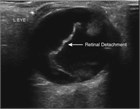

Patients may present with visual complaints of acute monocular floaters or flashes of light. The most common cause is a posterior vitreous detachment, but a retinal detachment or tear, cerebrovascular causes, and vitreous hemorrhage also must be considered. A retinal detachment requires urgent ophthalmology referral whereas a posterior vitreous detachment can be seen in follow-up. The history along with visual acuity, detailed ophthalmologic and fundoscopic exam, and bedside ultrasound can aid in the diagnosis.

retinal detachment